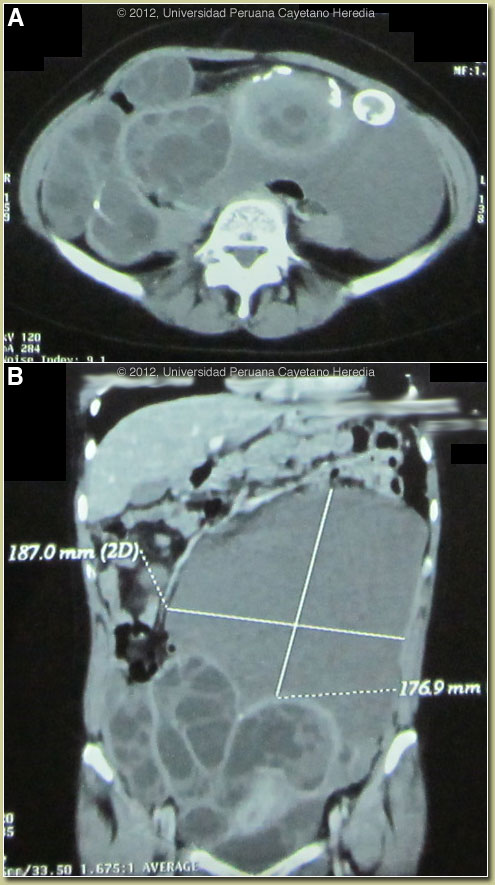

| Diagnosis: Echinococcus granulosis with multiple disseminated abdominal and pelvic hydatid cysts. |

Discussion: The large intraperitoneal multiseptate cysts on CT scan are diagnostic of hydatid disease. Older involuted cysts such as the one in the liver here show a characteristic calcification pattern. Western blot for E. granulosus was positive. Serology is usually positive with solitary hepatic cysts but sensitivity drops below 50% with solitary pulmonary cysts even when the cyst is large. With the large burden of disease in this patient’s liver and abdominal cavity a positive serology would be expected. Image C shows an intact large hydatid cyst and Image D shows a gross surgical specimen from a similar case from our files. Previous hepatic hydatid cases we have shown are Gorgas Cases 2003-03 and 2011-05. In adults the expectoration of salty-tasting fluid with or without pieces of white membranous material is highly characteristic of a fistula or frank rupture of a cyst into a bronchus, but children may not be able to describe this. On further questioning the patient recalled a compatible episode at the time of her episodes of hemoptysis.

Discussion: The large intraperitoneal multiseptate cysts on CT scan are diagnostic of hydatid disease. Older involuted cysts such as the one in the liver here show a characteristic calcification pattern. Western blot for E. granulosus was positive. Serology is usually positive with solitary hepatic cysts but sensitivity drops below 50% with solitary pulmonary cysts even when the cyst is large. With the large burden of disease in this patient’s liver and abdominal cavity a positive serology would be expected. Image C shows an intact large hydatid cyst and Image D shows a gross surgical specimen from a similar case from our files. Previous hepatic hydatid cases we have shown are